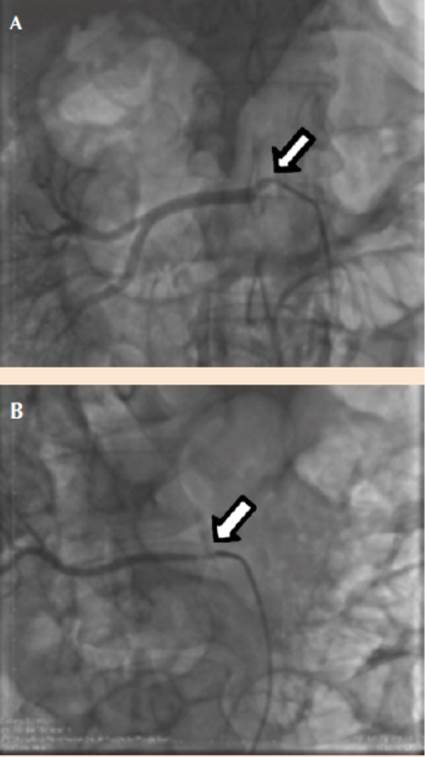

La angiografía renal realizada el 28 de octubre de 2016 arrojó los siguientes hallazgos: arteria renal izquierda con lesión ostial crítica de 90% de obstrucción. Dos arterias renales derechas, ambas con lesiones ostiales de 80%. Se observó arteria renal derecha accesoria (Figuras 1 y 2).

Figura 1 A. Estenosis ostial de la arteria renal derecha. B. Estenosis de la arteria renal derecha accesoria (flecha).